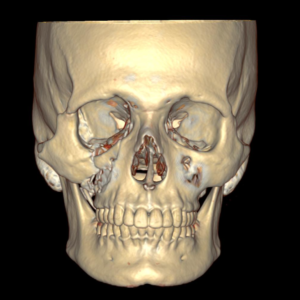

- Fraturas dos maxilares e órbita;

- Lesões craniofaciais (crânio, base do crânio e esqueleto facial);

O diagnóstico é feito pelo exame físico dos ferimentos e, nos casos de suspeita de fratura, deve se associar radiografias e tomografias computadorizadas. Esse avaliação poderá ser feita no hospital (se o paciente estiver internado) ou no consultório odontológico. O primeiro passo no tratamento é garantir a vida do paciente. O profissional deve garantir que o paciente esteja respirando bem e sem lesões graves que podem levar a morte rapidamente (como hemorragias severas, obstrução de vias aéreas e lesões de órgãos vitais)

A maioria dos ferimentos simples na pele pode ser tratada com anestesia local, limpeza da lesão e sutura. As fraturas da face e lesões complexas são tratadas sob anestesia geral. Os ossos quebrados são restaurados utilizando-se, geralmente, mini-placas e parafusos de titânio (que são biocompatíveis e não sofrem rejeição) que facilitam a recuperação e cicatrização óssea e dos tecidos